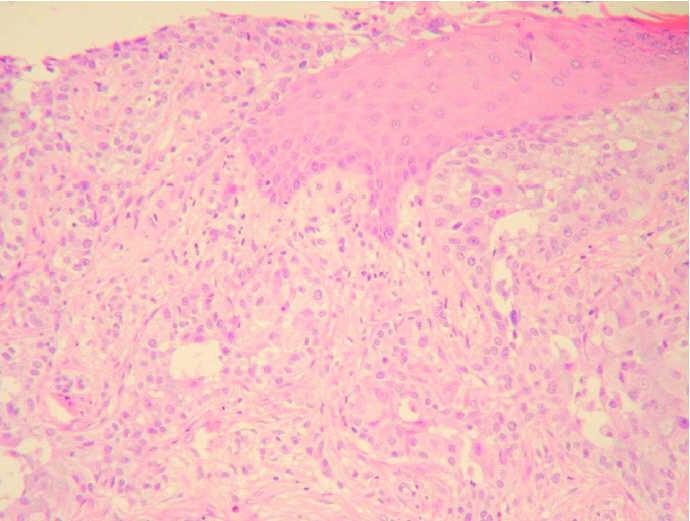

Fig. 4.--A mayor aumento se evidencian abundantes figuras de mitosis y atipias celulares. (Hematoxilina-eosina, ×200.)